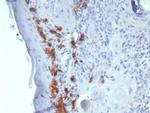

CD1a/HTA1 (Mature Langerhans Cells Marker) Antibody in Immunohistochemistry (Paraffin) (IHC (P))

CD1a/HTA1 (Mature Langerhans Cells Marker) Antibody (909-RBM13-P1ABX) in IHC (P)

Formalin-fixed, paraffin-embedded human skin stained with CD1a Mouse Recombinant Monoclonal Antibody (C1A/8111R). HIER: Tris/EDTA, pH9.0, 45 min. 2 °: HRP-polymer, 30 min. DAB, 5 min. {{ $ctrl.currentElement.advancedVerification.fullName }} 验证信息 View more